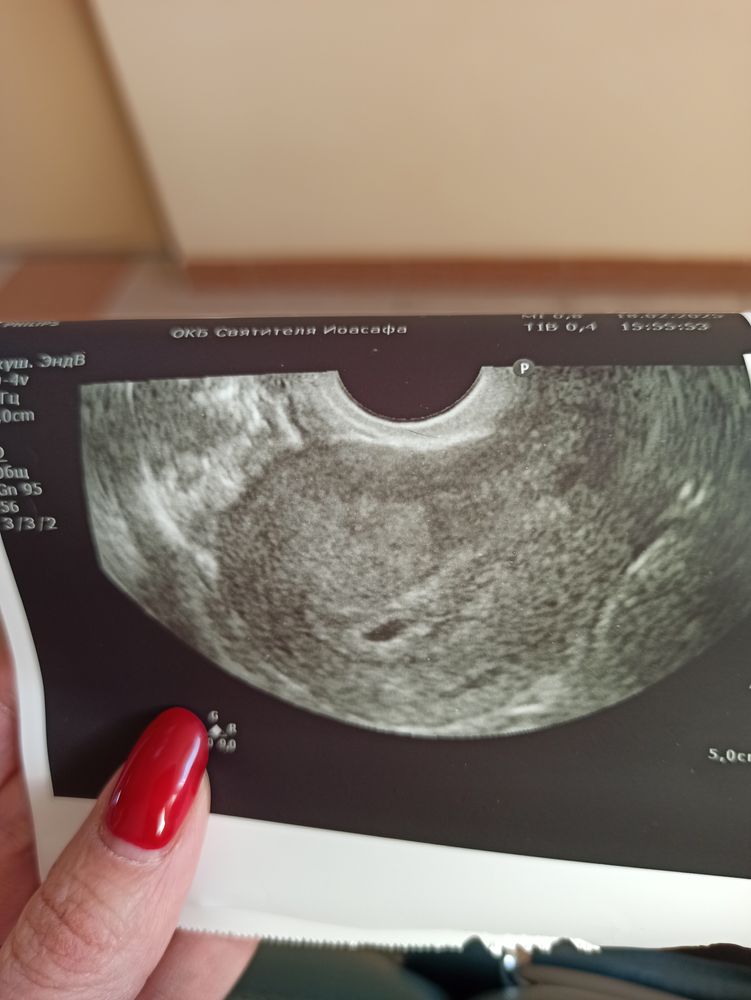

Вижу жм у вас 🙂

Тихонько поздравляю❤️